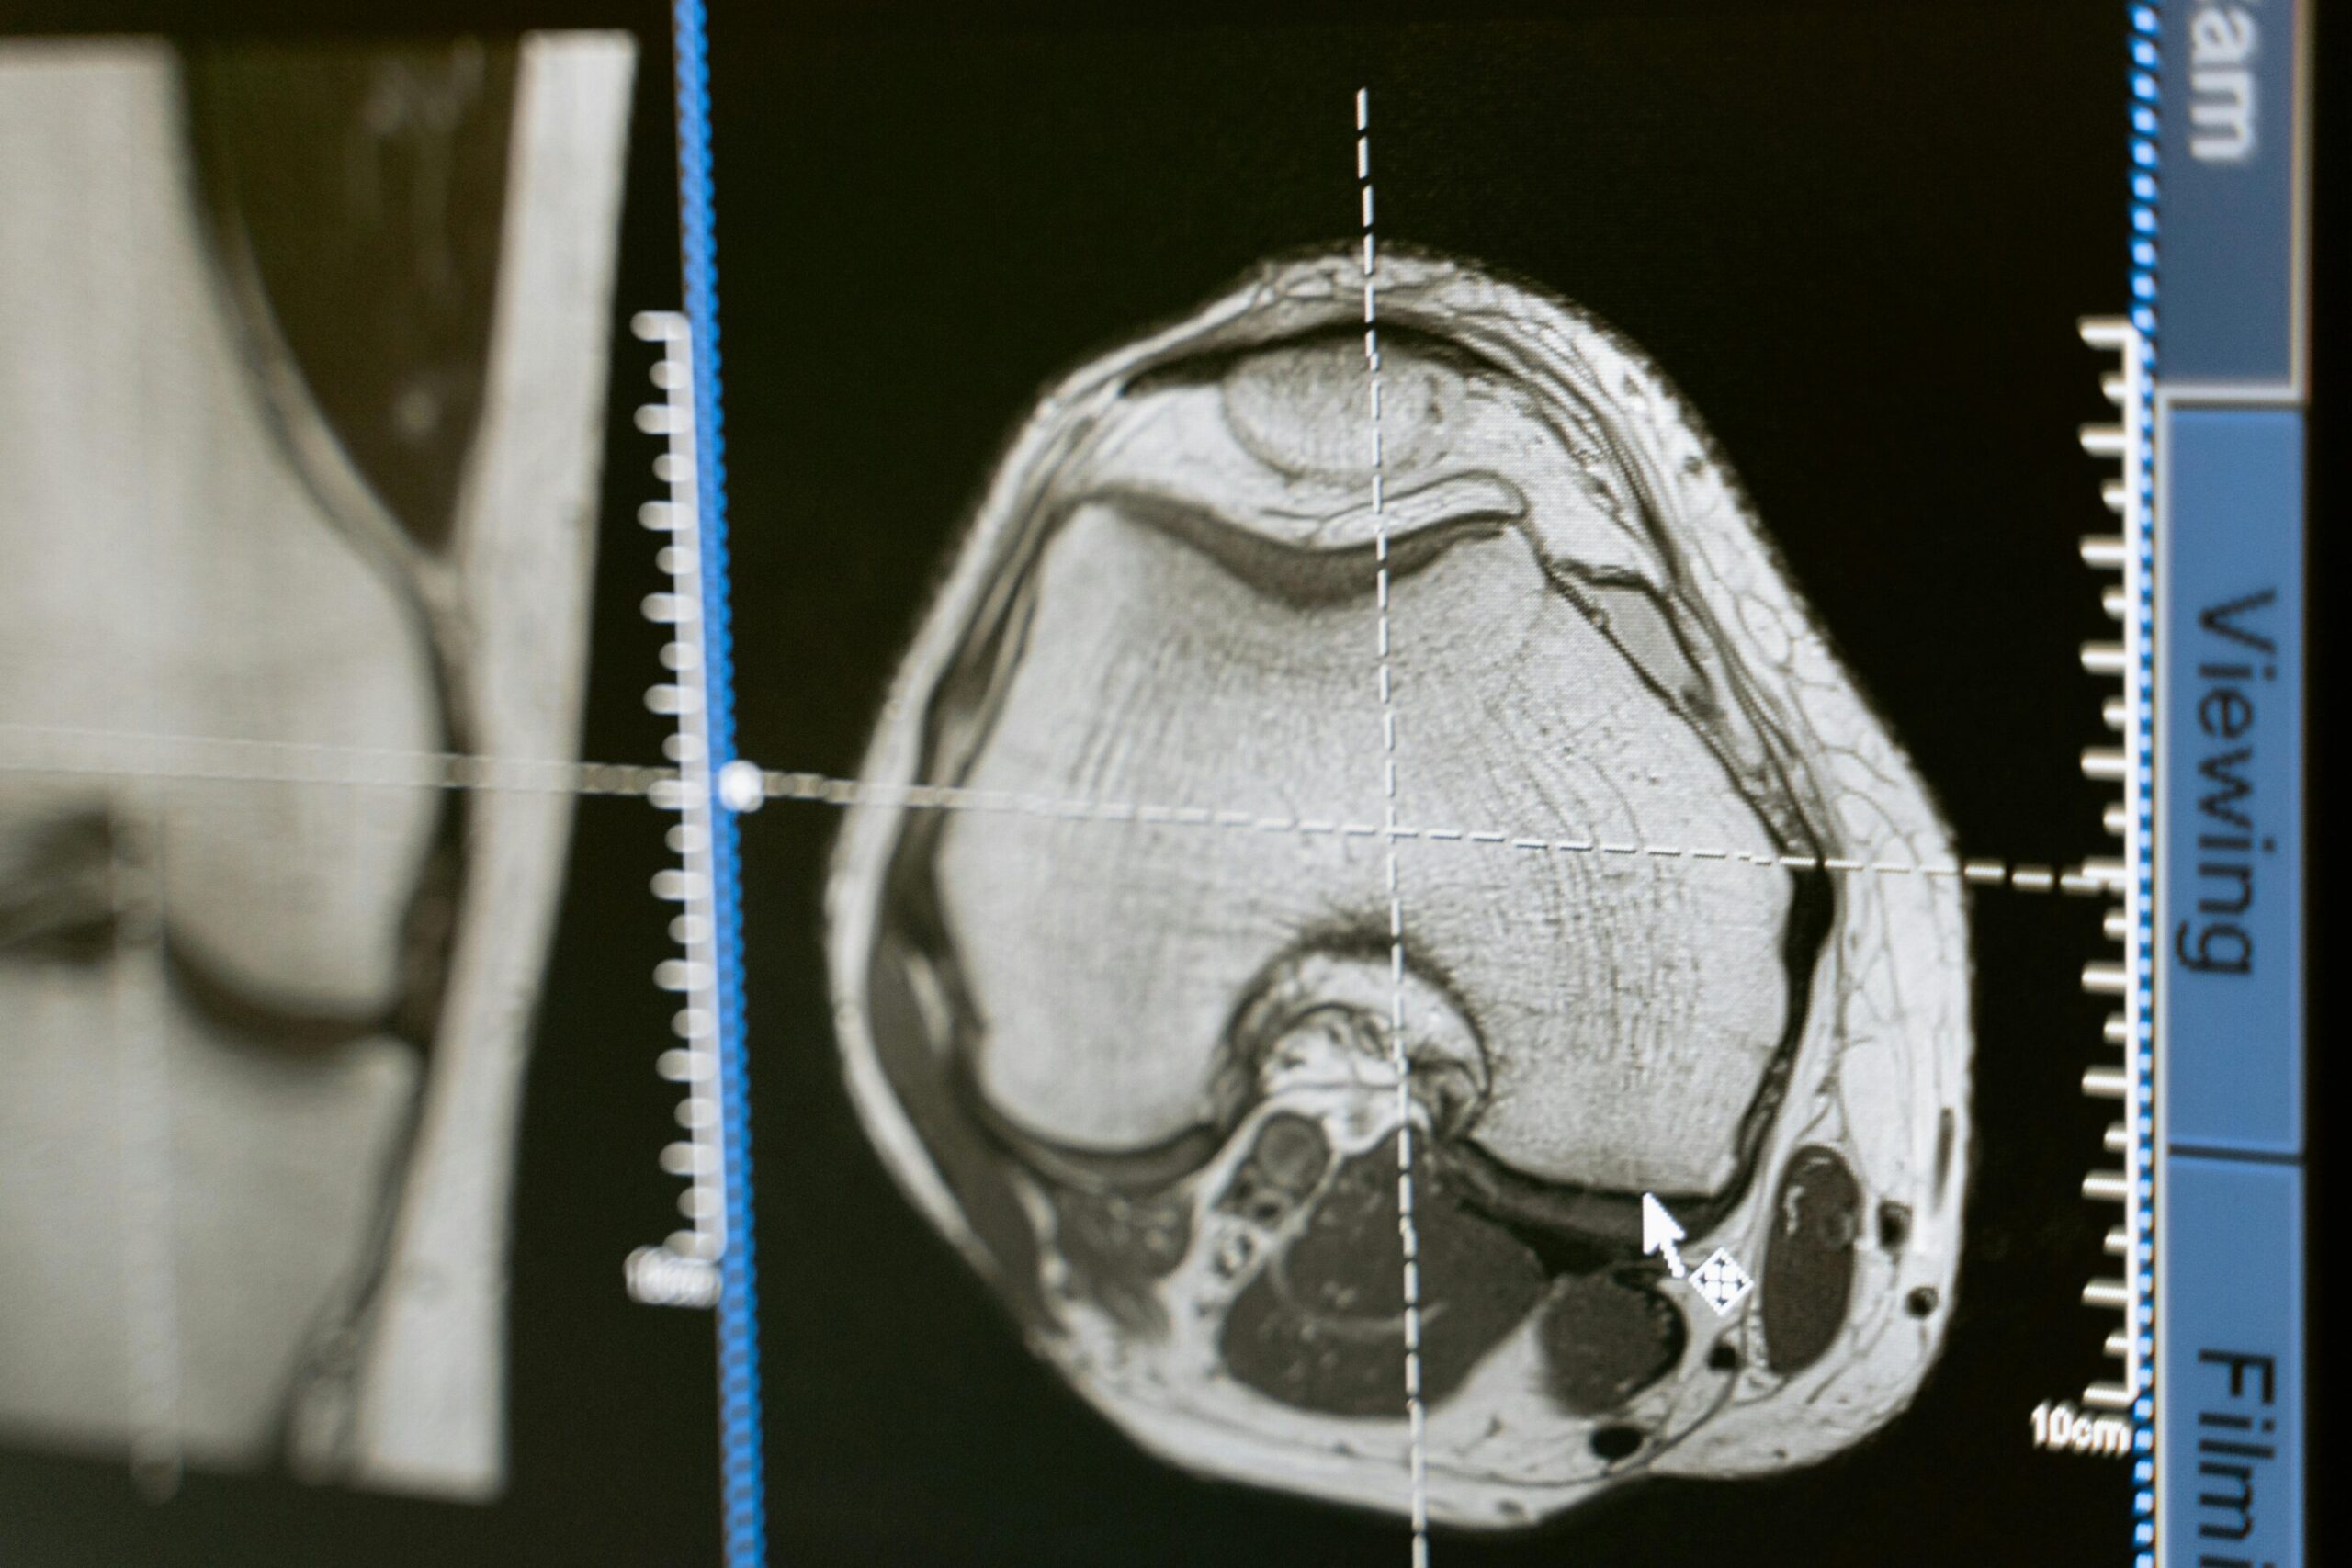

Dans une étude récente, une équipe de Mizzou dirigée par Jimi Cook, Ph.D., a découvert que les patients ayant des niveaux élevés de neuf protéines spécifiques – sont passés en collectant des échantillons d’urine – étaient beaucoup moins susceptibles d’avoir des résultats réussis d’une procédure de genou connue sous le nom de tissu sain à partir d’un donneur. Il s’agit d’une procédure qui utilise des solutions biologiques pour préserver l’articulation naturelle d’un patient plutôt que des remplacements articuliers en métal ou en plastique artificiel.

Cette découverte pourrait aider les patients souffrant de douleurs au genou à prendre des décisions plus éclairées sur le moment et le type de chirurgie qui leur convient le mieux.